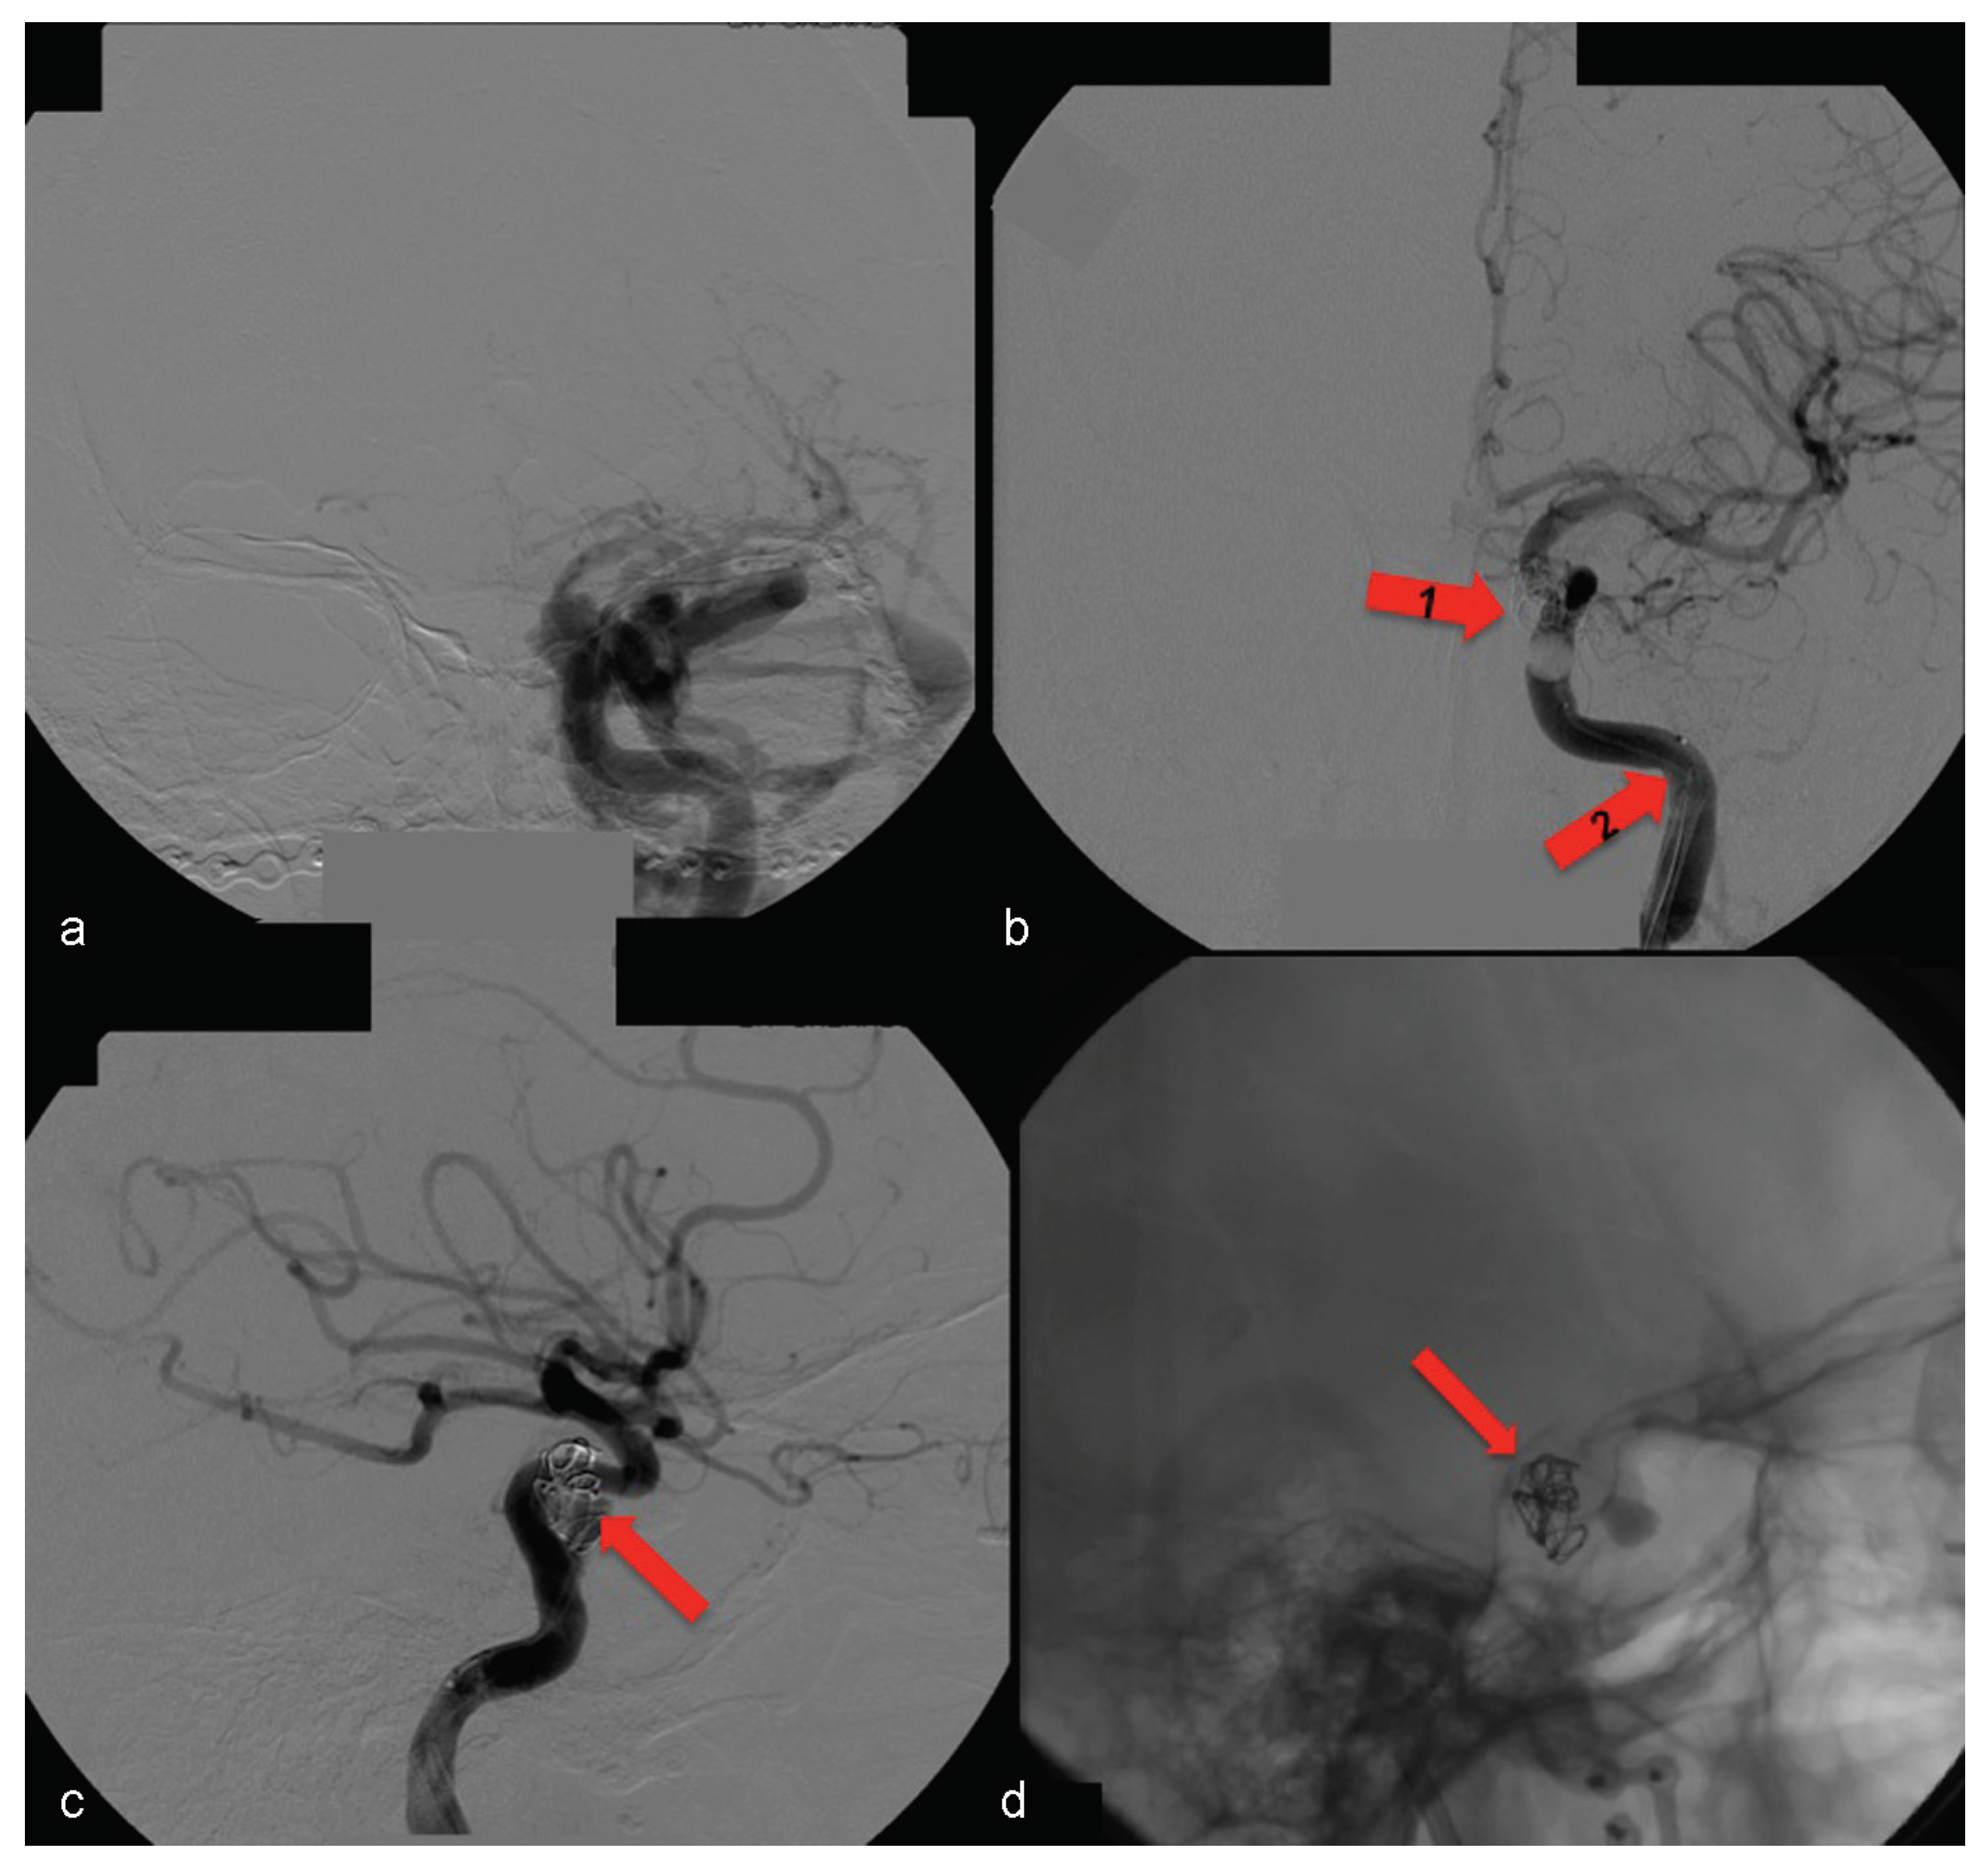

Examination of the patient showed normal results on the right side (Figure 7). The left side displayed significant alterations (Figure 8). It showed Type A CCF.

In this case, the right femoral artery was punctured for the bilateral carotid and vertebral angiography. Type A CCF was treated by embolization of the left traumatic cavernous aneurism using a Tracker Excel 14 microcatheter (Boston Scientific Corporation, Neurovascular Division, Freemont, CA) and a TS 14 microguide (Micro Therapeutics, Irvine, CA) to selectively catheterize the CS on the left side, by depositing nine detachable GDC microcoils (Boston Scientific Corporation) associated with a detachable balloon (Figure 9) inside it.

Figure 9. (a) Left side angiography, with coronal view, showing congestion toward the left orbit. (b) The same coronal view with occluded fistula— arrow no. 1 highlights the activated balloon and arrow no. 2 highlights the microcatheter. (c, d) Left side angiography, with sagittal view showing the detachable microcoils used for permanent carotid-cavernous fistula occlusion (arrows).